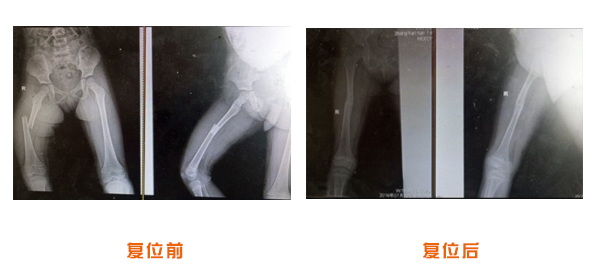

肥城市安駕莊梁氏骨科醫(yī)院是一所以梁氏手法正骨配合膏藥為特色的現(xiàn)代化專科醫(yī)院。

梁氏骨科術始創(chuàng)于清雍正年間,歷經八代,至今已有三百年歷史。據(jù)1929年泰安縣志載“梁瑞圖先生,字增生,號蓮峰,安駕莊人,精岐黃并發(fā)明接骨,凡跌打車凡跌打車軋皮不破而碎骨者......【詳細】 |